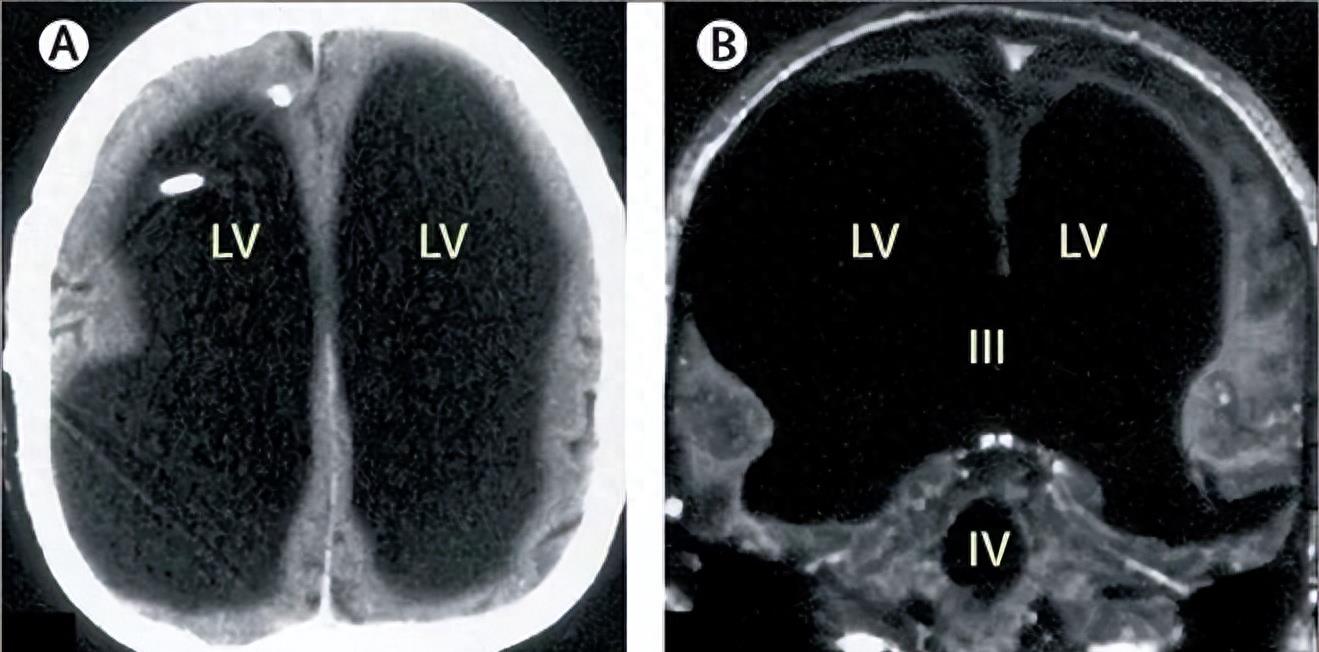

一个人在大脑缺失90%后,却依然过着正常人一样的生活。2007年,一名法国44岁男子觉得腿部无力,去医院做了个检查后,医生告诉他,他大部分脑子都缺失了,头骨全是液体,只剩下一层薄薄的脑组织。然而,他依然有家庭,有工作,智商为87,和正常人没什么区别。这个医学奇迹让我们重新审视了大脑的神秘和弹性。